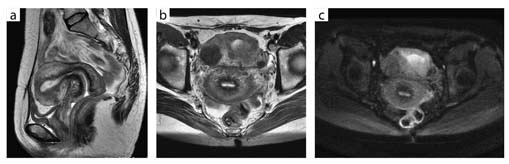

図4 多発性子宮筋腫(32chボディアレイコイル)

a:T2WI,FOV 20cm,スライス厚 5mm,1分57秒

b:T2WI,FOV 20cm,スライス厚 5mm,1分40秒

c:DWI,b値1000,スライス厚 5mm,1分45秒

奥田:骨盤領域,特に婦人科領域については,3Tでは磁場の不均一によってなかなか良好な画質が得られない,あるいはTRを長めに設定しないと1.5Tと同じようなコントラストが得られないため,撮像時間が延長すると言われていました。TRは6000ms程度に設定する必要があるとの報告もありましたが,Discovery MR750では,4500ms前後で1.5Tと同等のコントラストが得られています。加えて,空間分解能は3Tの方が高いので,より細かい部分の観察が可能となりました。なかでも,子宮筋層の内膜側にあるjunctional zoneのコントラストが,TRを延長せずに1.5Tと同じような感覚で描出できることには大変驚きました。

また,骨盤腔は消化管の動きとガスの影響を受け,磁場の不均一が起こりやすいと言われています。そこで,3Tでは鎮痙剤の使用が必須と言われていましたが,Discovery MR750では鎮痙剤を使用しなくても安定した画質が得られています。ただ,消化管がガスで著明に拡張している場合などは,画質に影響することもあります。

2.撮像時の工夫

● 骨盤領域(前立腺)への臨床応用

谷本:前立腺は,1.5Tでもそれなりに高画質が得られますが,3Tでうまく撮れたときの美しさにはかないません。例えば,以前撮像した例では,前立腺外腺の導管構築1本1本が鮮明に描出され,直腸内コイルを用いた高分解能MRI以上のきわめて高画質が得られました。ただ,やはり直腸にガスが大量にあるような例では,少しアーチファクトが出ることがあります。そのため,現状では前処置は行っていませんが,将来的には,最初の位置決めスキャンで直腸内に大量のガスが確認された場合は,前処置を行うことも検討するかもしれません。

また当院では,3TではLAVA-FLEXを用いて前立腺のダイナミックMRIを行っています。拡散強調画像を撮像する際のb値は1000と1500で1.5Tと同じですが,S/Nは大幅に向上しています。